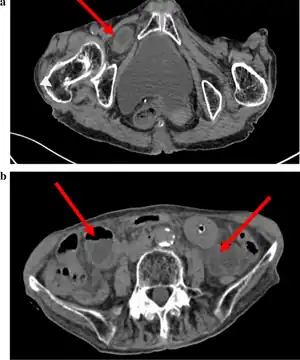

| Abdominal CT scan showing obturator hernia[1] | |

The diagnosis is often made during laparoscopic pelvic exploration after the person arrives at the hospital with signs and symptoms consistent with bowel obstruction. Laparoscopic pelvic exploration is a minimally invasive procedure that allows the surgeon to visually examine the contents of the abdomen without making a large cut.[5] The Howship–Romberg sign is suggestive of an obturator hernia, with about 56.2% (out of 146 patients in a systematic review) of people showing these signs.[2] These signs are worsened by thigh extension, medial rotation and abduction.[6] It is described as a sharp, stabbing pain in the medial thigh/obturator distribution, extending to the knee and is caused by the hernia pushing on the obturator nerve. The Hannington-Kiff sign can also be suggestive of an obturator hernia, which tests the adductor muscle reflex with a hammer whilst applying pressure on the obturator nerve.[7] However, due to its rare form, obturator hernias are difficult to diagnose due to many other possibilities, non-specific symptoms of pain, as well as minimal external signs/symptoms that can be seen without imaging. The current gold-standard for diagnosis of an obturator hernia is through abdominal computed tomography scans (CT scans), which has been used for diagnosis of 84.2% of patients in a recent systematic review for obturator hernias.[2]